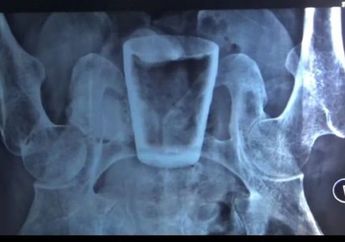

Mengeluh Kesakitan hingga Tak bisa Beraktivitas Selama 3 Bulan, Ternyata Benda Ini Ada di Dalam Perut Pria Asal Jember, Tim Dokter: Kemungkinan Masuk Lewat Anus

3 Tahun yang lalu - Sakit tak kunjung sembuh selama tiga bulan, ternyata setelah rontgen penyebabnya adalah benda ini yang ada di dalam perutnya.